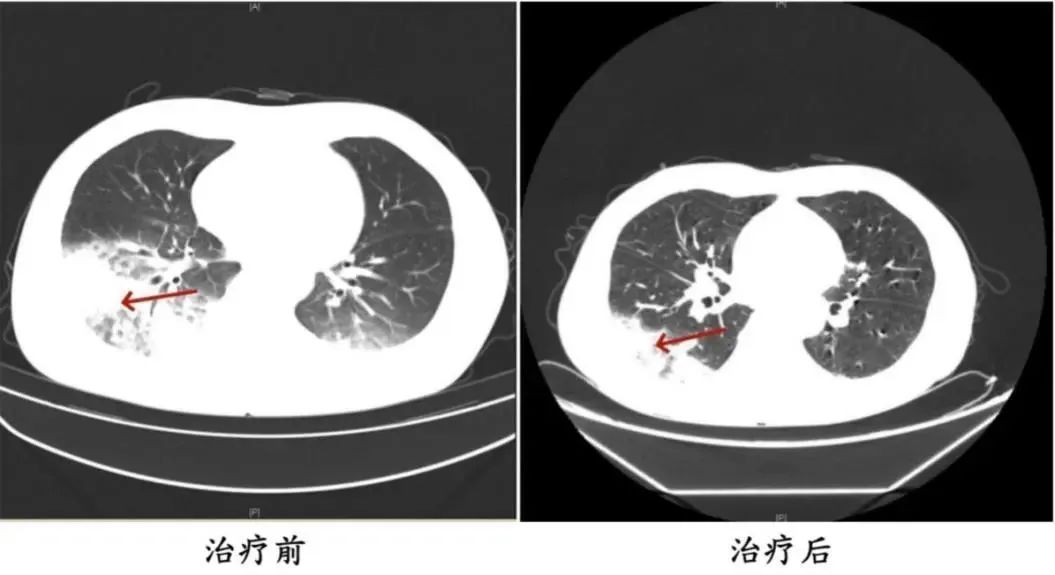

治療前后陳先生肺部CT影像

醫(yī)師判斷病人有可能感染軍團菌,建議病人健全纖支鏡檢查,留下肺泡灌洗液標(biāo)本查找病原菌。最終,病人肺泡灌洗液NGS(Next-Generation Sequencing,下一代測序)檢測結(jié)果顯示:嗜肺軍團菌,早期診斷為軍團菌肺炎。醫(yī)師立即調(diào)整治療方法,改用能覆蓋嗜肺軍團菌的一線藥物抗感染,病人體溫逐漸下降,第二天體溫恢復(fù)正常,經(jīng)后續(xù)治療后康復(fù)出院。